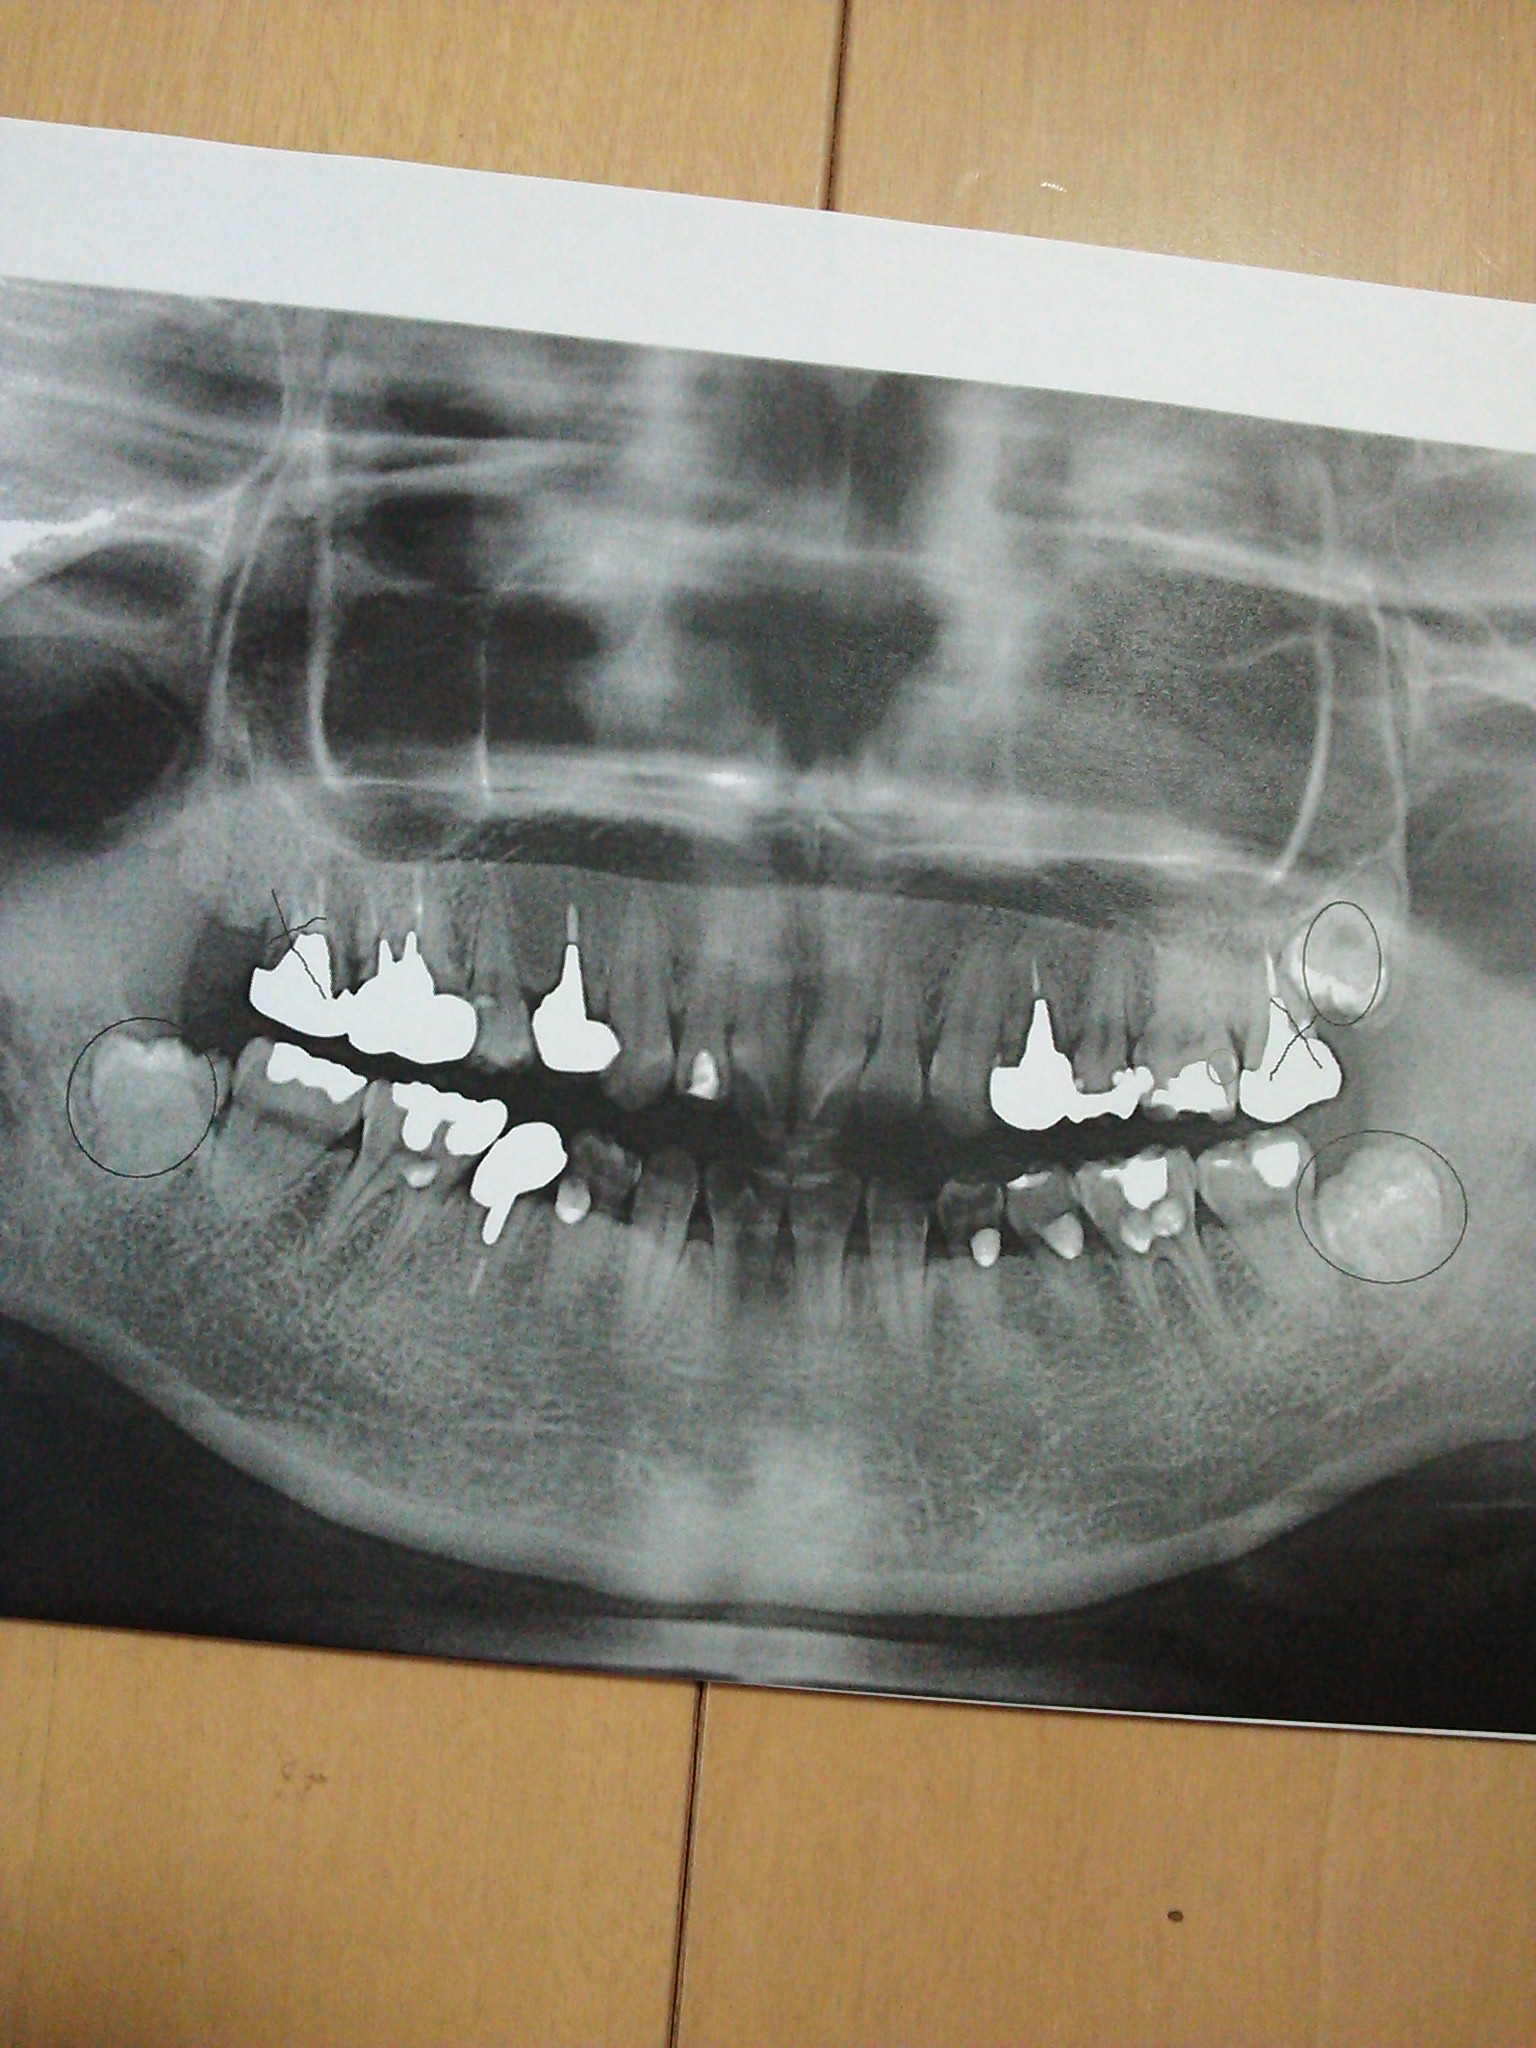

全体の画像

画像1DSC_0608.JPG

CTを撮った結果、膿が溜まっていて骨も溶けてる、おそらく歯も2つに割れてるだろうから抜歯と言われました。

全体の画像は何故か印刷しかできないと言われて紙をもらってきました。